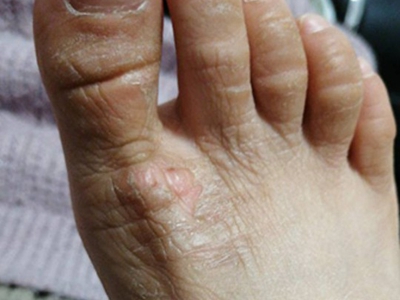

干性湿疹症状图片

干性湿疹又称乏脂性湿疹、裂纹性湿疹,多发生在秋、冬、春三季,由气候干燥、皮肤水分脱失、皮脂分泌减少所致,以皮肤干燥、干裂伴脱屑为主要临床表现。多见于老年人,好发于小腿,也可发生于双上肢等部位。

干性湿疹表现为皮肤干燥,有细裂纹,呈淡红色,浅表皲裂性皮肤类似“碎瓷”样。部分患者会出现瘙痒,不断抓挠后容易出现浅表糜烂、出血及结痂,轻者伴少量细碎的鳞屑,重者有较多的白色大片鳞屑脱落。